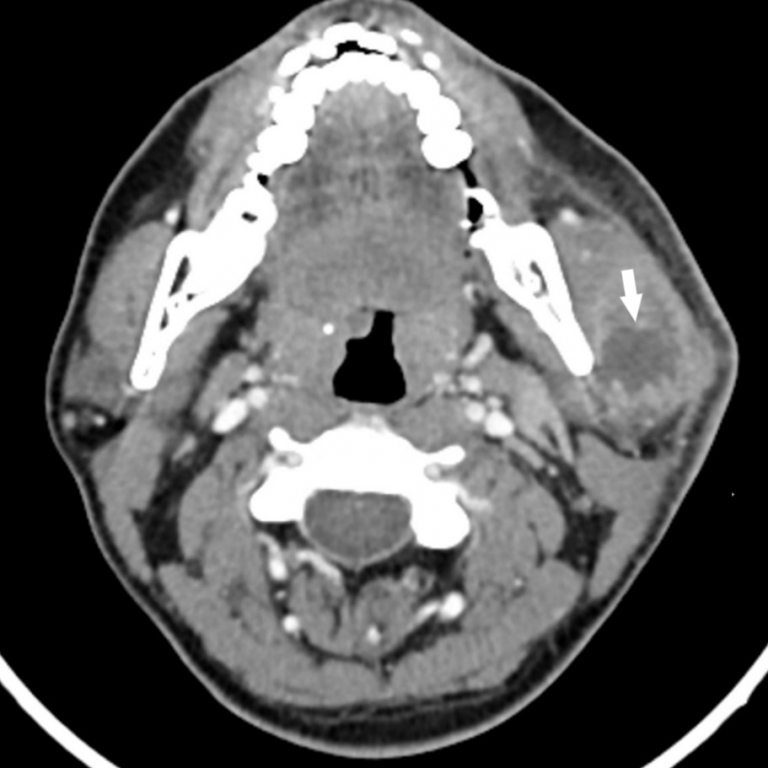

Trismus was present, with restricted and painful mouth opening of approximately 2 cm. Serous saliva of normal consistency was observed flowing from the Stensen’s duct orifice. No additional significant findings were noted on physical examination. Neck ultrasonography revealed a dense fluid collection of approximately 3×2 cm within the left parotid gland, suggestive of an abscess. To further evaluate potential post-traumatic fractures, the extent of abscess spread, its origin, and involvement of cervical spaces, contrast-enhanced neck computed tomography (CT) was performed. A well-defined collection measuring approximately 3 cm in diameter, consistent with an isolated abscess within the left parotid gland, was observed (Figure 2).